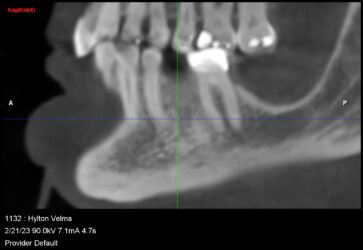

Hey guys just wanted to get to know your thoughts on what I can do to improve. This is a 78 yr old patient with controlled diabetes/hypothyroid/high BP. She takes her medications regularly and reports to be controlled. #29 was extracted due to fracture in October 2022 with bone graft. Implant Astra Osseospeed EV size 3.6×9 was placed in…

I created a deeper osteotomy today and placed a larger longer implant after removing the failed implant and thoroughly curetting and irrigating with CHX. Any guidance and feedback is welcome.